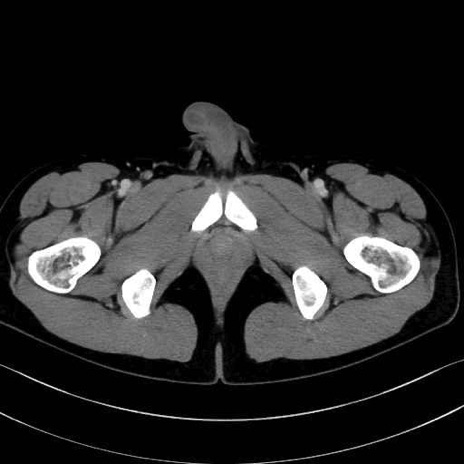

肛門挙筋 (Levator ani)

3. 殿部の筋肉(表層・中層・深層)

大殿筋 (Gluteus maximus)

内閉鎖筋 (Obturator internus)

外閉鎖筋 (Obturator externus)